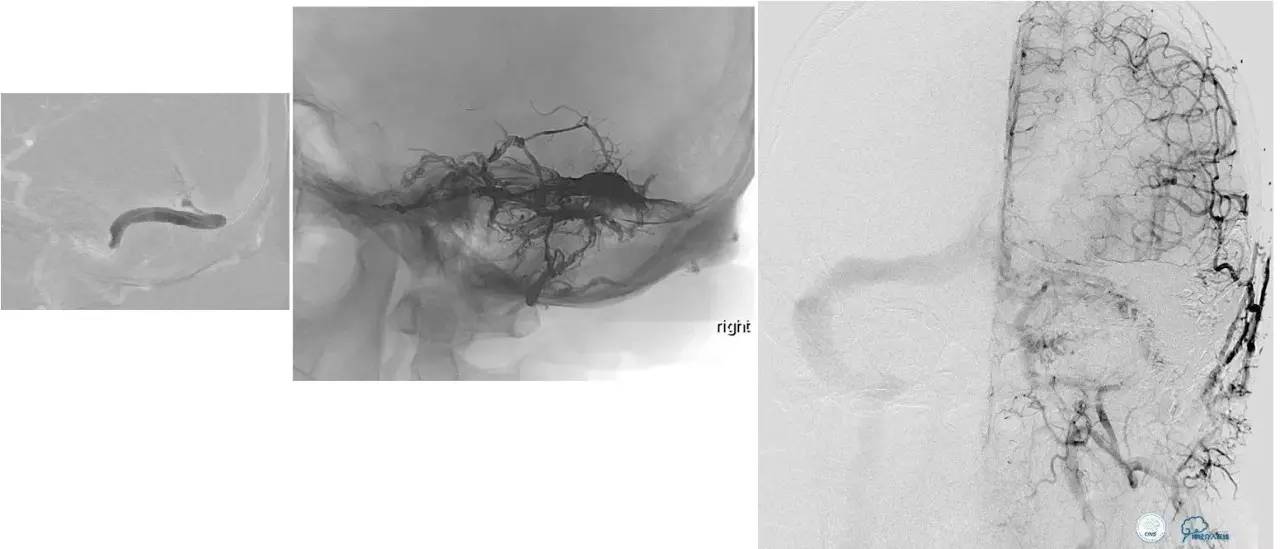

小脑幕缘区DAVF,只有颈外动脉参与供血,供血支细小。

选择抑制血管栓塞,胶无法弥散进入瘘口,选择另一支血管,近端防止Hyperform球囊。

最终胶弥散结果,瘘口完全消失。

小脑幕缘区DAVF,颈外动脉和颈内动脉的供血支均非常细小。

Marathon微导管进入分支后,在主干血管内放置Hyperform球囊。

最终的栓塞结果。